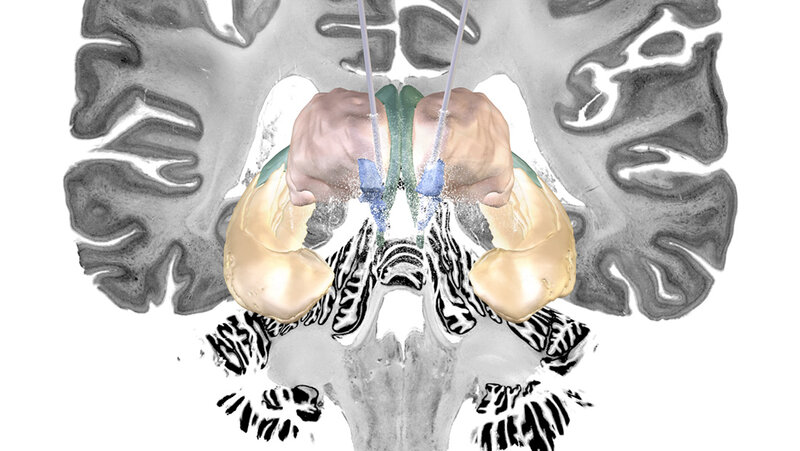

Das Forschungsteam um Prof. Horn konnte aber bei denjenigen Alzheimer-Patientinnen und -Patienten, bei denen die THS anschlug, die genaue Position der Elektroden anhand der Bilddaten im Nachgang exakt bestimmen. „Sie liegt an einer Zweigstelle zwischen zwei Nervenfaserbündeln – dem Fornix und der Stria terminalis –, die tiefgelegene Hirnregionen miteinander verbinden. Beide Strukturen werden mit der Gedächtnisfunktion in Verbindung gebracht“, erklärt der Neurowissenschaftler.